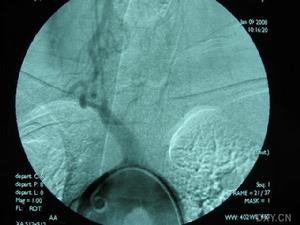

2.數字減影血管造影(DSA)重點觀察主動脈弓兩側鎖骨下動脈及頸總動脈等血管。若發現鎖骨下或頭臂幹上,椎動脈起始部的近心段有嚴重狹窄(多為管腔的85%)或幾乎閉塞,甚至同時可見造影劑經對側椎動脈上行至基底動脈又下行(逆流)至患側鎖骨下動脈的遠心段更可確診。

主動脈縮窄SSS確診主要靠腦血管造影,為避免血管造影時引起椎動脈起始段功能性狹窄,有條件的地方,最好行全腦血管造影以明確診斷。經股動脈穿刺腦血管及患側上肢血管造影可明確閉塞部位,有利於外科手術治療。對於急性鎖骨下動脈閉塞者,最好於閉塞後3天內行取栓術,有利於血液再通,避免再次栓塞。本組1例取栓術後至今已4年,配合抗凝治療,未再出現缺血症狀。大多數作者對SSS手術治療有較好的評價,鎖骨下與頸總動脈架橋術,是治療本症最常用的方法。對於少數長期狹窄的SSS患者且無急性腦損害者,尤其是壯年患者,可試用抗血小板聚集劑(6個月或以上)以及病因治療觀察。經顱多普超聲(TCD)可以連續及動態觀察椎動脈、基底動脈血流方向和速度,觀察顱內其他動脈被盜血的影響程度,是盜血綜合徵的敏感指標,可以評價治療效果和隨診。